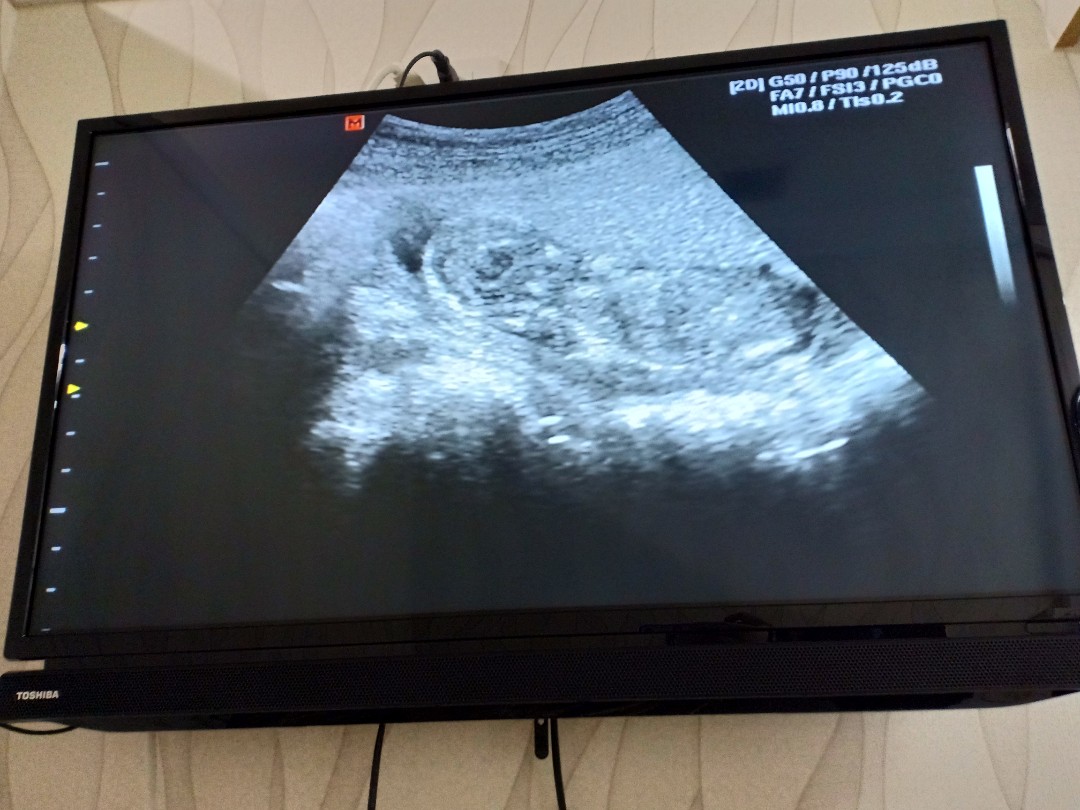

12 weeks ค่ะ